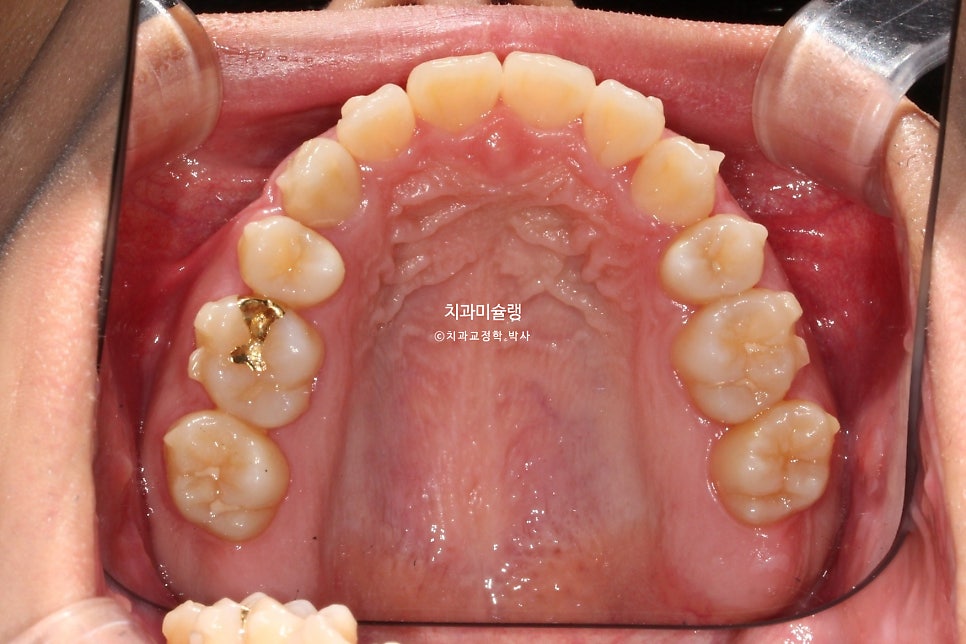

2026년 2월 치료 완료

중심선은 정확히 맞으며 앞니 교합은 좋습니다.

어금니 교합은 물샐틈 없는 1급 교합관계를 보입니다.

치료 결과 비교

이제 전후 비교 볼게요.

총 치료기간은 2년이 채 안걸린 1년 11개월 이며 총 내원 횟수는 10회 입니다.